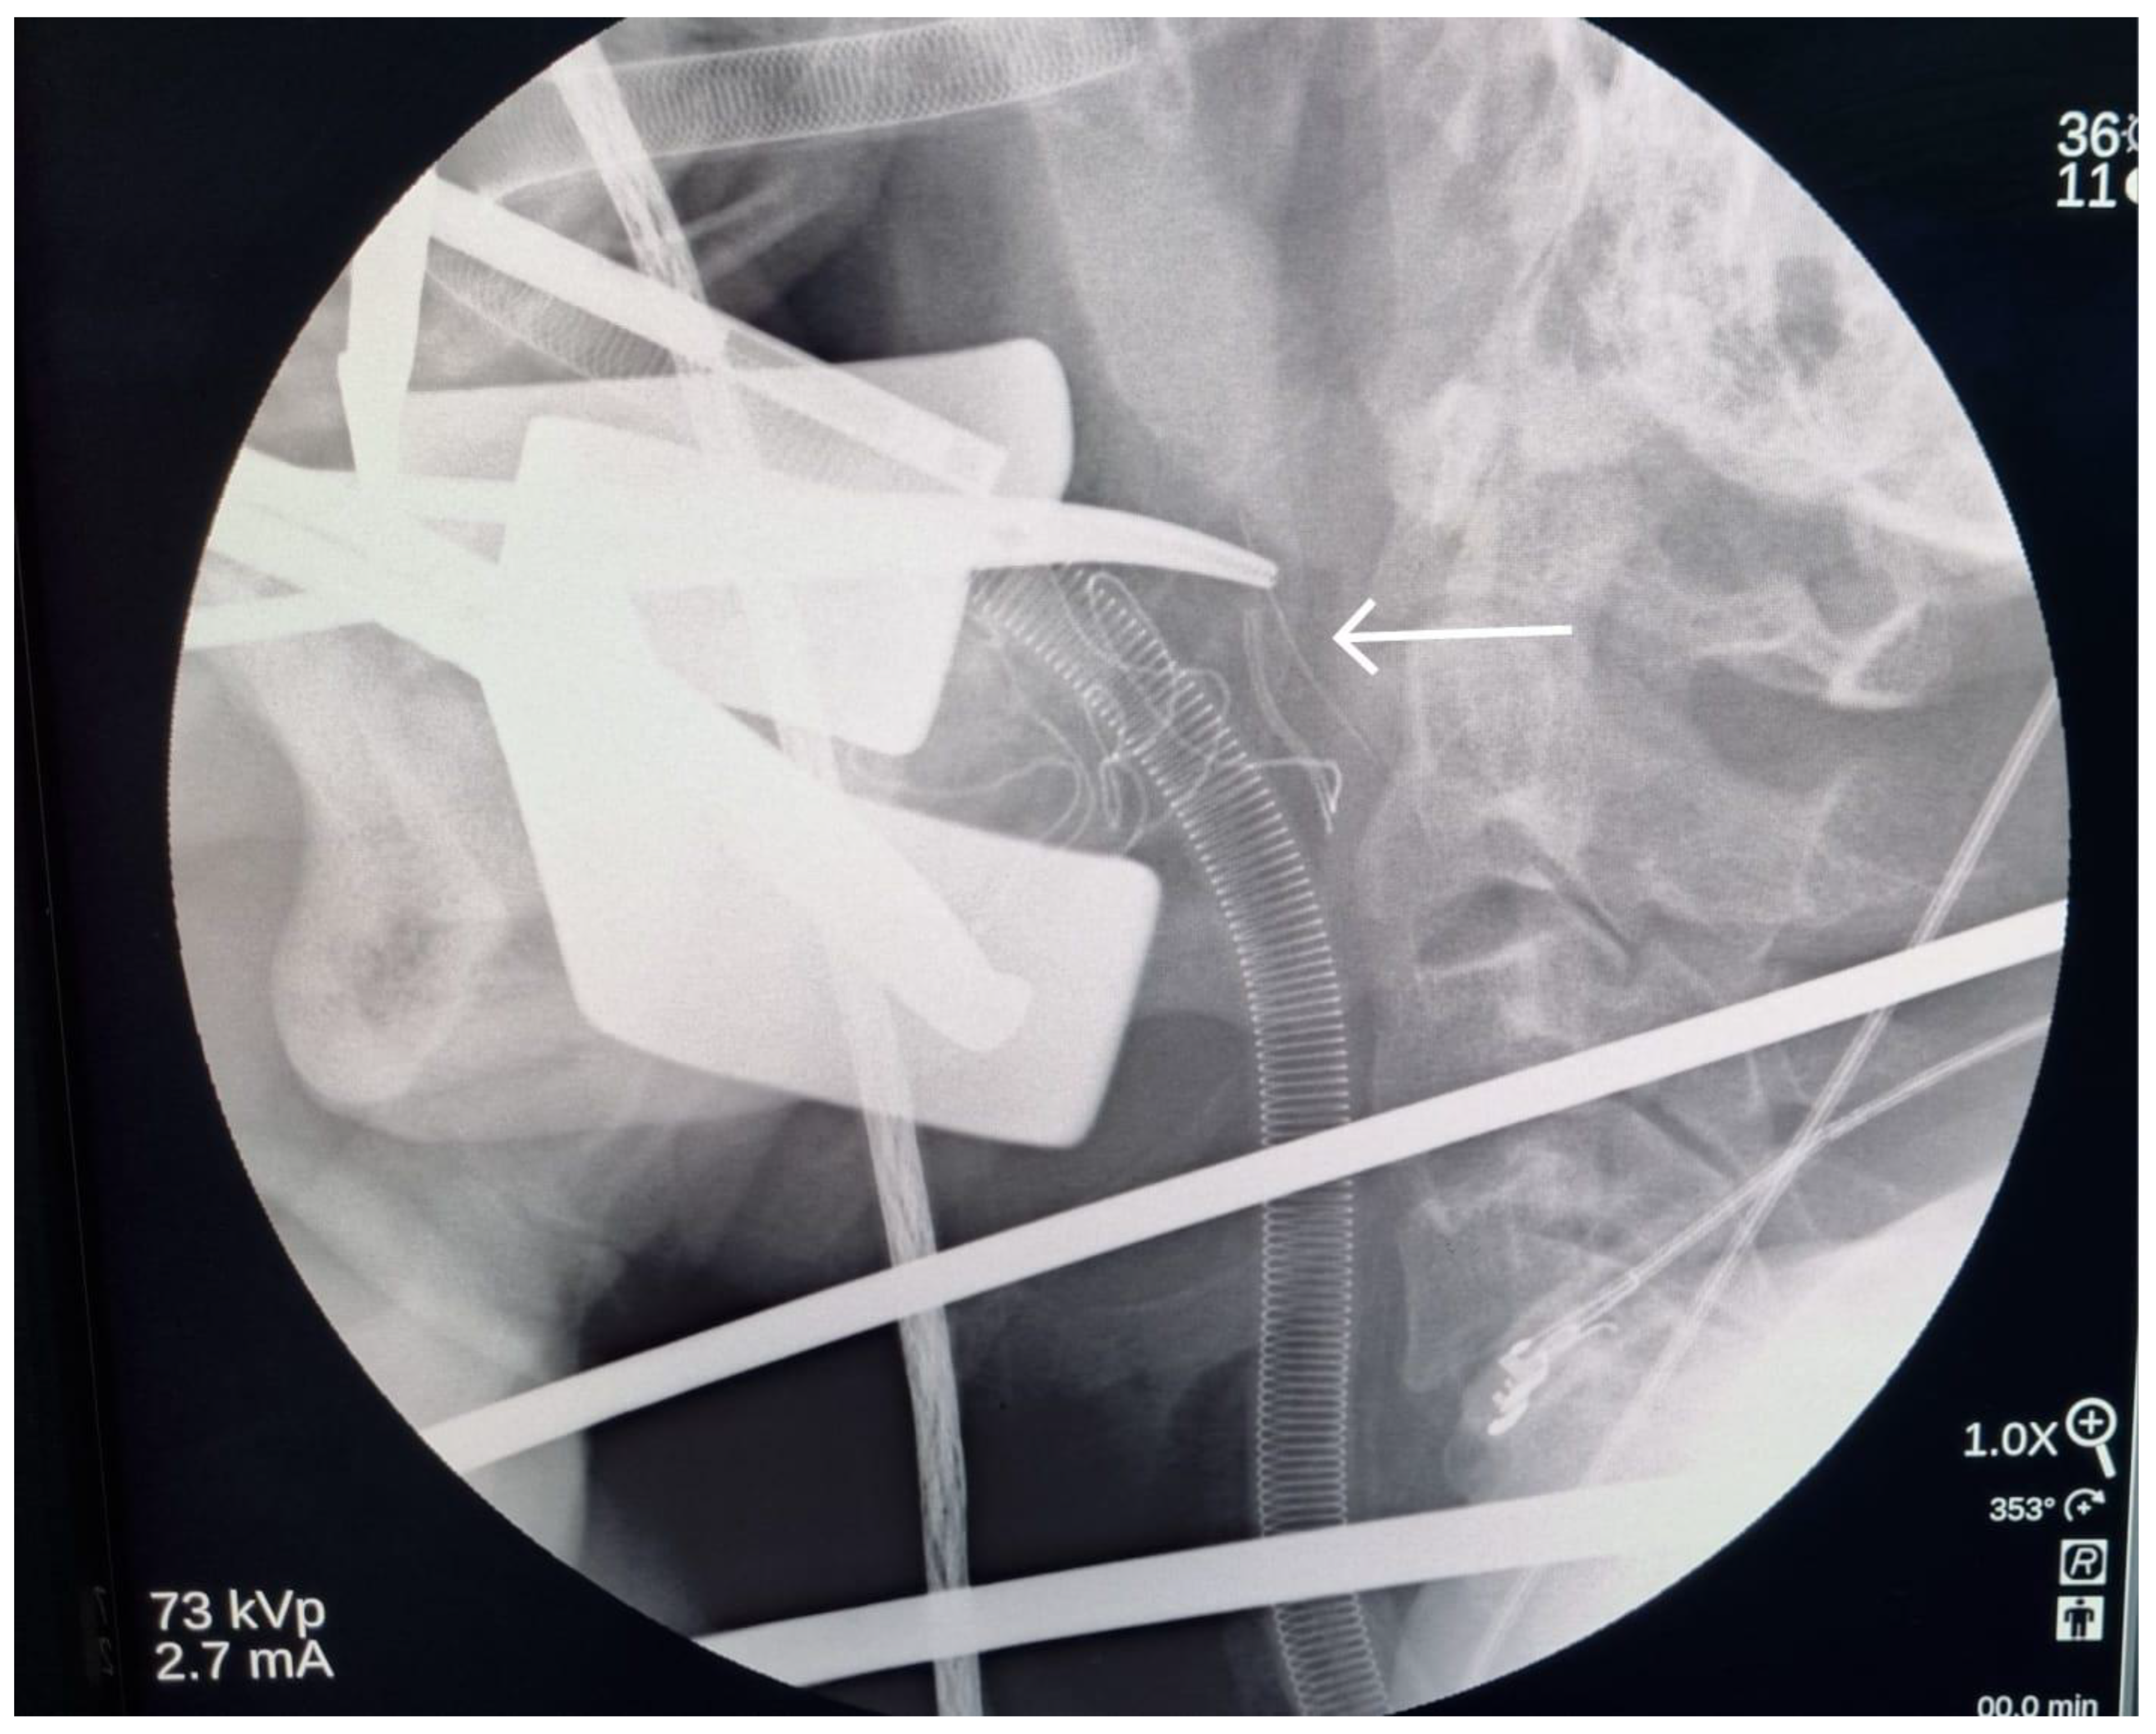

A Case of Broken Local Anesthetic Needle in the Pterygomandibular Space; Diagnostic Approaches and Surgical Management